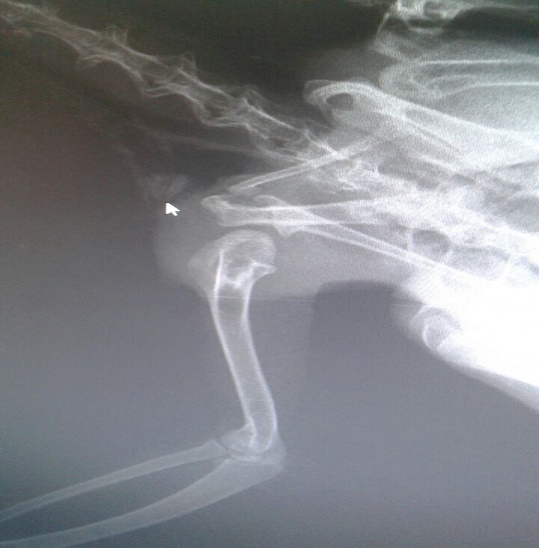

La evaluación radiográfica lateral derecha izquierda, evidenció una masa radio opaca, única no infiltrante que presuntivamente puede ser una neoplasia y no de un absceso caseificado (Figura 1).